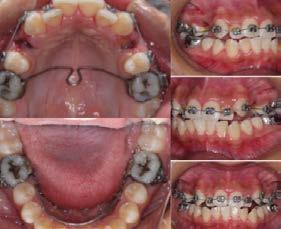

c) Estudio y análisis tomográfico en tercera dimensión del cráneo a nivel maxilar y mandibular (Figura 24).

de las aparatologías adecuadas para preservar o en su caso, recuperar el espacio, considerando la edad del paciente y la complejidad del caso a tratar37,38 (Figura 25).

24.

Figura

1. La existencia y presencia de todos los elementos anatómicos craneodentofaciales (Figura 26).

3. Los desplazamientos óseos, como consecuencia de su crecimiento endocondral o intramembranoso en las diferentes zonas o áreas de remodelación, aposición y reabsorción (Figura 27).

Todos los cambios dimensionales de los huesos faciales y su consecuente movimiento y remodelación, están íntimamente relacionados con los estímulos fisiológicos que activan las matrices funcionales de crecimiento, por la presencia de todos los elementos anatómicos (como los caninos), de manera adecuada, en coordinación con los demás elementos que conforman el sistema estomatognático y el sistema respiratorio35,36 (Figura 28).

Al estar ausente algún germen dental (como los laterales superiores permanentes y/o premolares de ambas arcadas, “los de mayor incidencia”),10 se inhibe la estimulación adecuada en el desarrollo óseo de esa zona específica, ya que al no existir el germen dental, la matriz ósea inhibe su crecimiento en esas zonas en específico11 (Figura 29).

Figura 25.

Figura 26.

Figura 27.

Figura 28.

maxilomandibulares, 17 las cuales propician alteraciones en el proceso del intercambio dentario; en la que una reducción de los espacios necesarios para el acomodo de los caninos y de otros órganos dentales en las arcadas, retrasa e impide que el impulso natural propio de la formación radicular como empuje fisiológico, impidiendo el desplazamiento y la erupción del canino en tiempo y una posición ideal dentro del arco dental (Figura 30).

Sumado a lo anterior, la retención generada dentro del macizo óseo basal altera su posición en angulación y dirección correcta de erupción. Situación que en ocasiones daña las raíces de los dientes adyacentes al canino y que finalmente podrá quedar incluido, en el peor de los casos, cuando no encuentra una salida de emergencia hacia el paladar o el vestíbulo12 (Figura 31).

consideraciones a tomar muy en cuenta como factor etiológico en la inclusión del canino (Figura 32).

Por otro lado, al haber una pérdida prematura de un diente deciduo, además de generar una disminución de la longitud del arco dental, la biomecánica fisiológica propia de nuestro organismo, tiende a cerrar los espacios o brechas generadas por la pérdida de algún órgano dental, mesializando los dientes distales al diente faltante y generando extrusión del antagonista inmediato (Figura 33).

Figura 29.

Figura 30.

Figura 31.

Figura 32.

Figura 33.

Figura 34.

Figura 35.

Figura 36.

4. Los tiempos biológicos en el cierre de crecimiento óseo39 (Figura 38).

Otra consideración a valorar, son los malos hábitos, entre los que se encuentran con más frecuencia los deletereos y que recaen en la mayoría de las complicaciones para la erupción de los caninos. El tiempo, perseverancia, permanencia e intensidad de estos malos hábitos será proporcional a las alteraciones óseas que se generen, parafunciones musculares y respiratorias, desplazamientos dentales y la consecuente maloclusión presente al momento de realizar el diagnóstico definitivo previo al plan de tratamiento22 (Figura 39).

acomodo no fisiológico lingual, etc.; lo cual, refleja un acompañamiento del subdesarrollo en el cuerpo y rama mandibular, el cual es un factor crítico para el acomodo de los caninos en la etapa del intercambio dental23 (Figura 40).

Figura 37.

Figura 38.

Figura 39.

Figura 40.

1. Arco extraoral, el cual pude ser utilizado con tracción alta, media o cervical.40,41 Péndulo o aparato de Hillgers modificado (Figura 41).

2. Mascara facial (Figura 42).

3. Bionator simple o combinado con lip bumper, entre otros (Figura 43).

Figura 41.

Figura 42.

posicionada en dirección vestibular, ya que solamente el 17% de caninos impactados vestibularmente tienen un espacio suficiente, a comparación de los impactados donde la corona tomó la dirección hacia el paladar, ya que por lo regular en estos casos, el canino deciduo siguió estando presente sin reabsorción alguna, el cual desempeña un papel importante como mantenedor de espacio biológico; sin embargo, genera la necesidad de que el canino busque una salida emergente, que en estos casos es hacia la bóveda palatina44 (Figura 44).